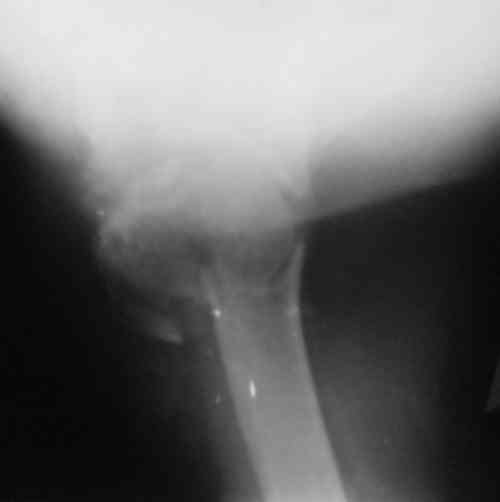

Судя по снимкам головка ротирована,успех закрытой репозиции, на мой взгляд, сомнителен, надо оперировать.

Судя по Р-граммам имеется оскольчатый перелом головки плеча. Во время открытой репозиции имеется большой риск "развалить" перелом, что значительно ухудшит кровоснабжения отломков. А так, на мой взгляд контакт м\у отломками достаточный, не смотря на наличие ротационного смещения головки думаю лучше продолжать консерватикное лечение. С уважением.

Судя по снимкам еще имеется перелом головки плеча, и чрезкостный отрыв вращательной манжеты. Для уточнения характера перелома не иешало бы сделать КТ. Если вести консервативно, то после сращения перелома будет ограничение движений в суставе не устраивающее больную. Я склоняюсь к оперативному лечению( накостный остеосинтез Т- Г образная пластина, лучше LCP для проксимальног плеча, обязательно подшить на место манжету).

В соответствии с работами Neer данный перелом можно классифицировать как однофрагментарный, так как нет диастаза более 1 см и углового смещения более 45 градусов - такие переломы лечатся консервативно. Рентген контроль каждые 10 дней- если смещение не увеличивается, то через 3-4 недели разработка движений в суставе

Уважаемый Сергей! Вы правильно написали критерии, но недооценили степень смещения в переломе хирургической шейки. Посмотрите ещё раз, это Two part fracture.